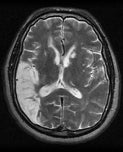

Wat is neurologie?

Neurologie is de medische tak die zich bezighoudt met ziekten en aandoeningen van het zenuwstelsel. Dit omvat problemen met de hersenen, het ruggenmerg, het hersenvocht, de perifere zenuwen en spieren.